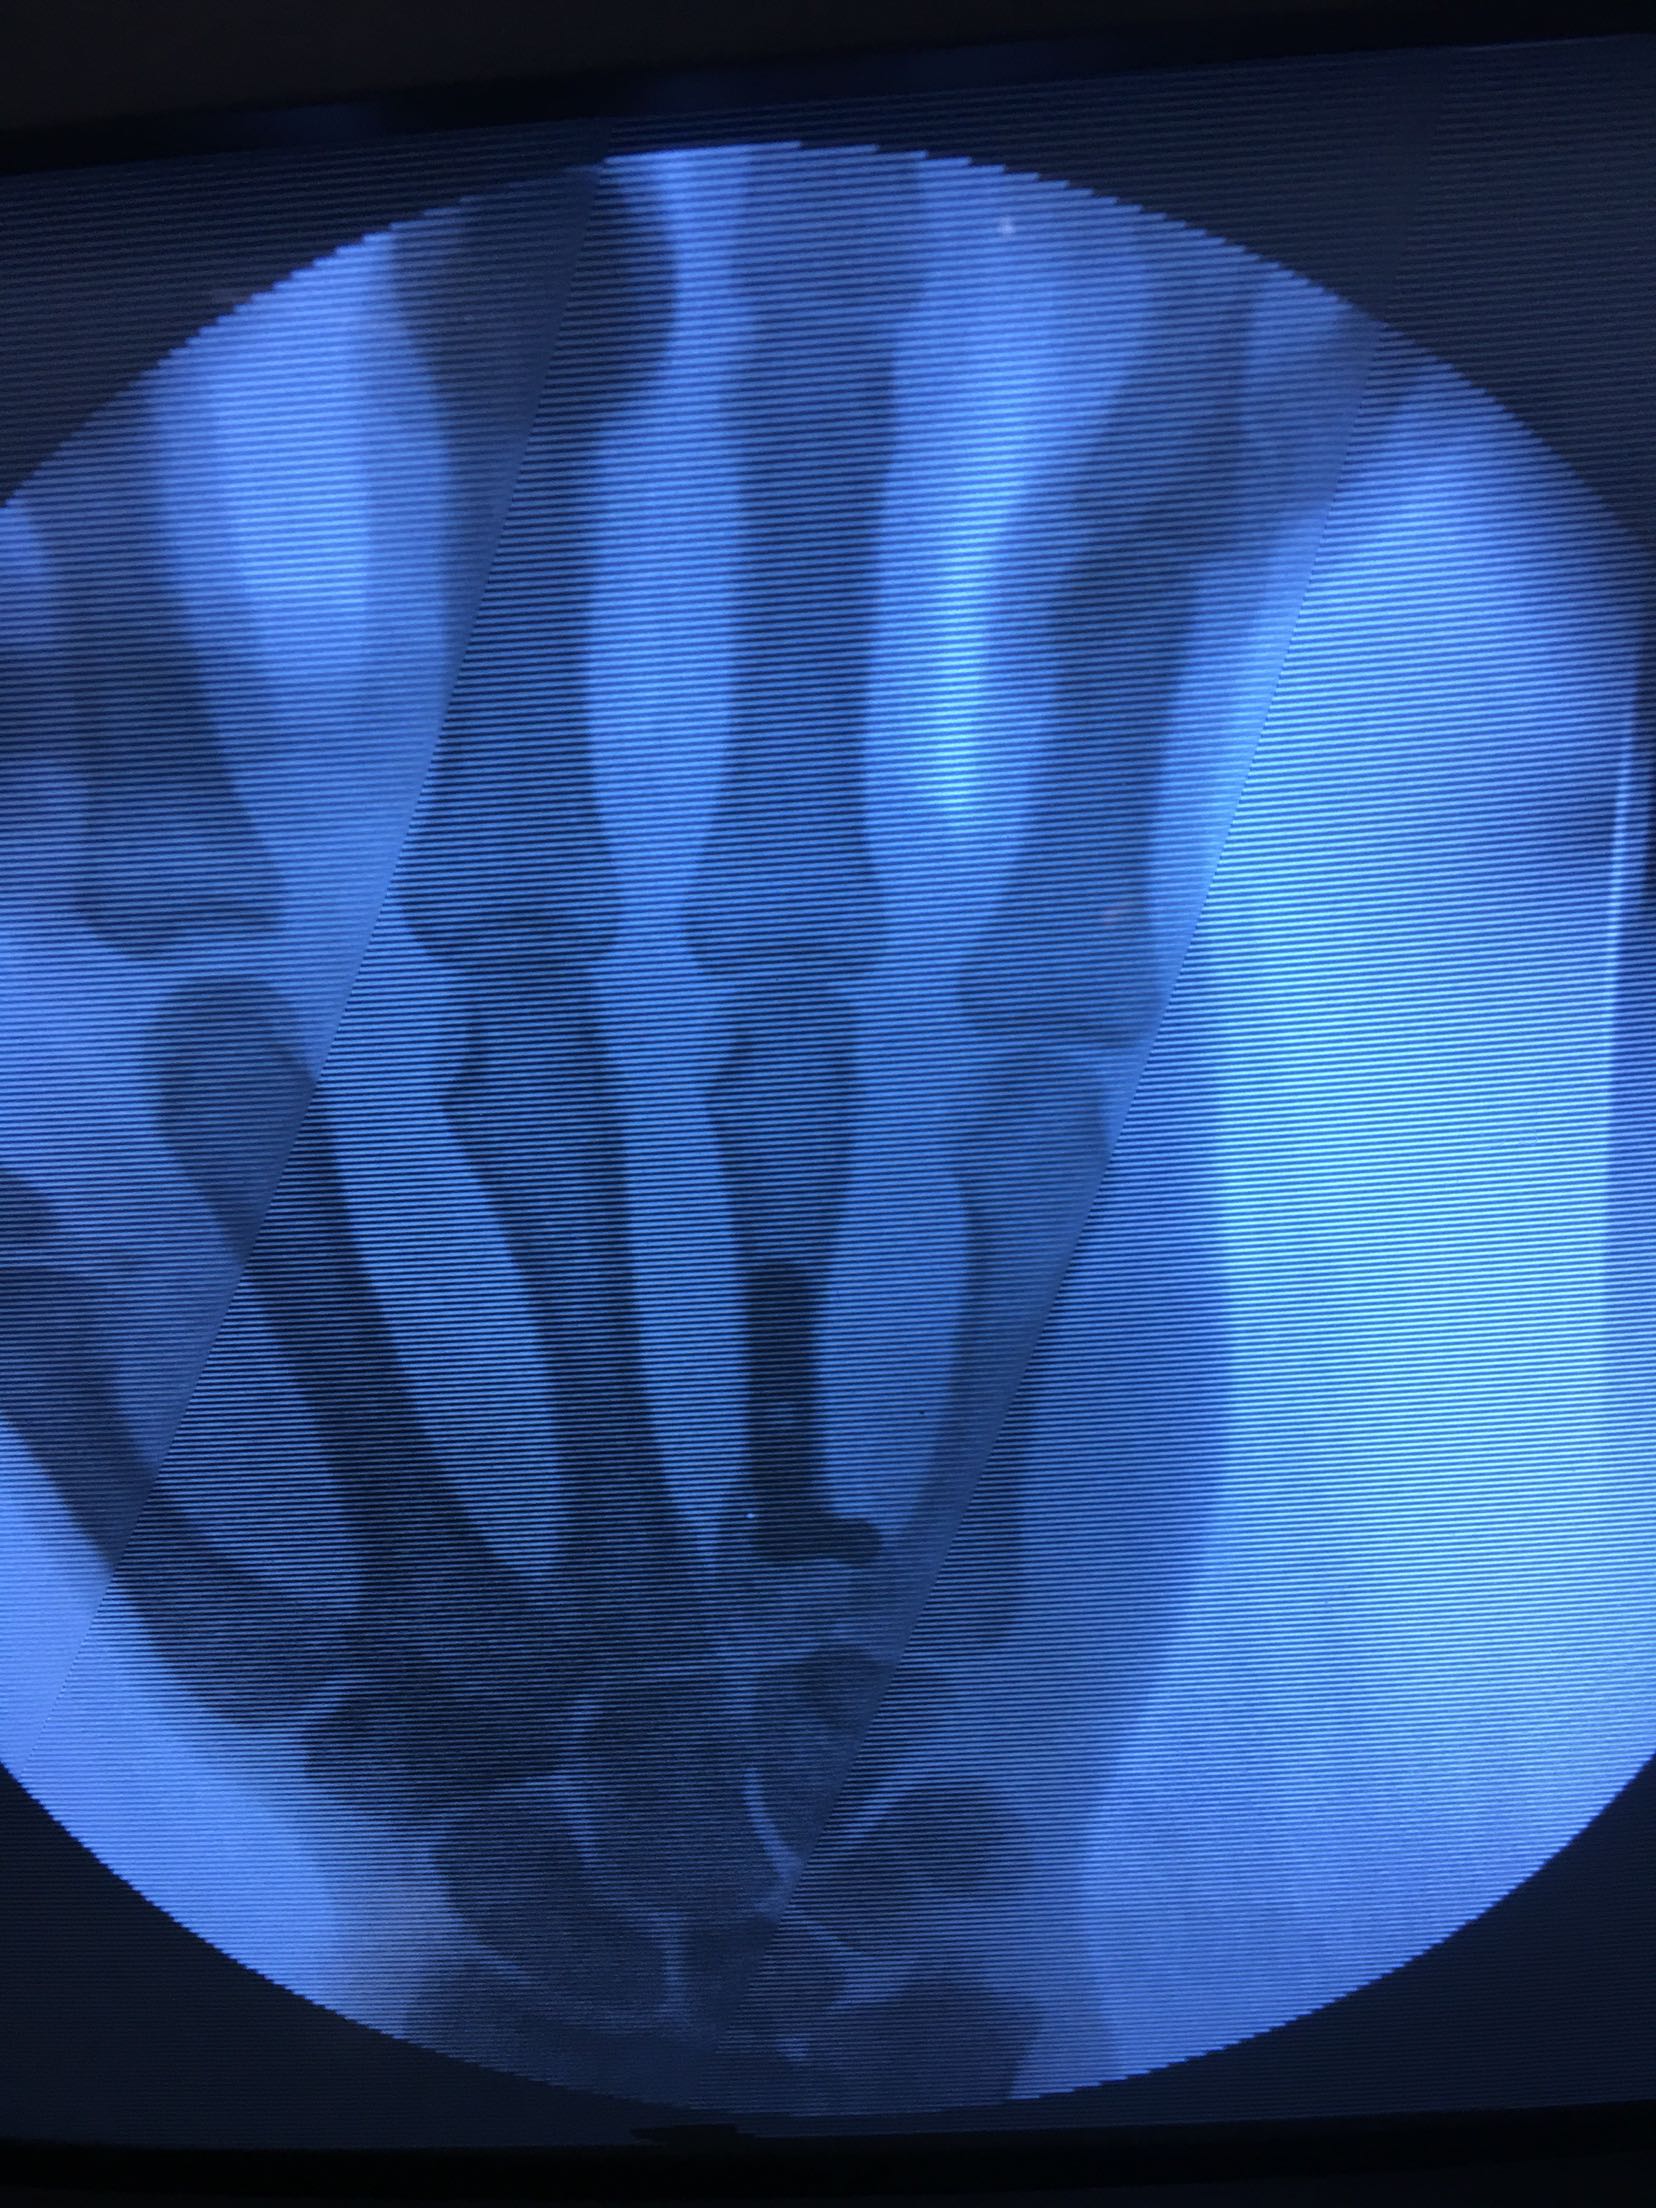

患者,男,52岁,摔伤后右手肿痛,活动受限4小时入院。

右手掌肿胀明显,皮色皮温正常,局部压痛,纵叩痛阳性,可及骨擦感,第四掌指关节活动受限,末梢血运感觉正常。

完善检查,在臂丛麻醉下行切复内固定术,术后抗炎,消肿止痛处理。